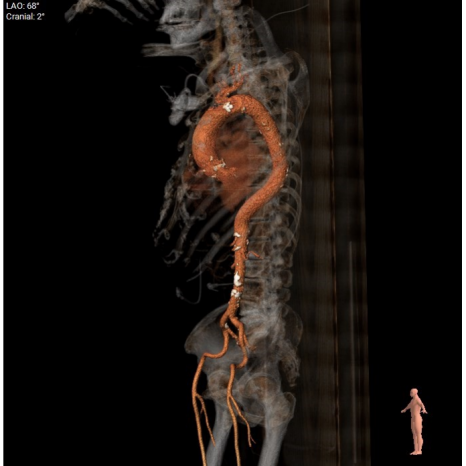

4.胸腹主动脉走形呈S形迂曲,管壁散在混合型斑块